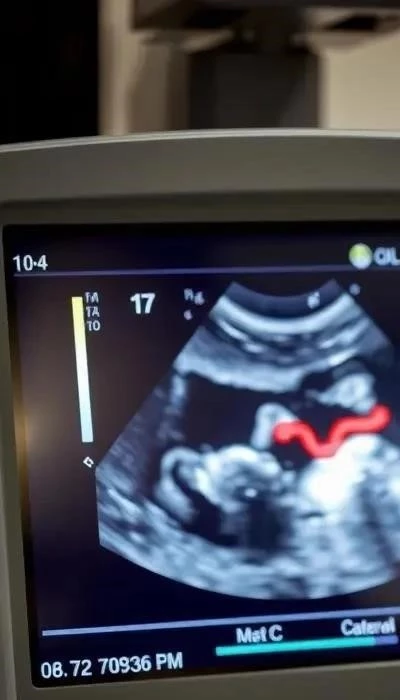

Ультразвуковое исследование (УЗИ) – основной визуализирующий метод. Трансвагинальное УЗИ обладает высокой разрешающей способностью при подозрении на эктопическую беременность. Ключевые УЗИ признаки включают:

- Отсутствие плодного яйца в полости матки при подтвержденной беременности (положительный тест, рост ХГЧ).

- Визуализация образования, подозрительного на плодное яйцо, вне матки – чаще в маточной трубе (трубная беременность). Это может быть анэхогенное/гипоэхогенное включение с желточным мешком или эмбрионом.

- Свободная жидкость в позадиматочном пространстве, указывающая на кровотечение.